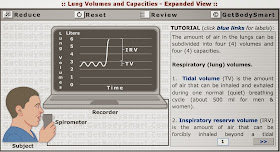

11 . LA CAPACIDAD PULMONAR

Volumen corriente (VC). Es el volumen de aire que normalmente entra en una inspiración o sale en una espiración. En los hombres es de 0,5 litros.

Volumen de la reserva inspiratoria (VRI). Es el volumen de aire que entra de más en una inspiración forzada. En los hombres es de 3 litros.

Volumen de la reserva espiratoria (VRE). Es el volumen de aire que sale de más en una espiración forzada. En los hombres es de 1 litro.

Capacidad vital (CV). Es el volumen de aire que se puede espirar tras una inspiración forzada. Equivale a la suma de los tres anteriores volúmenes (VC + VRI + VRE = CV). En los hombres es de 4,5 litros.

Volumen residual (VR). Es el volumen de aire que siempre queda en el interior de los pulmones. En los hombres es de 1,5 litros.

Capacidad pulmonar total (CPT). Es la máxima cantidad de aire que pueden acoger los pulmones. En el hombre son 6 litros.

Práctica

Capacidad pulmonar

Capacidad pulmonar